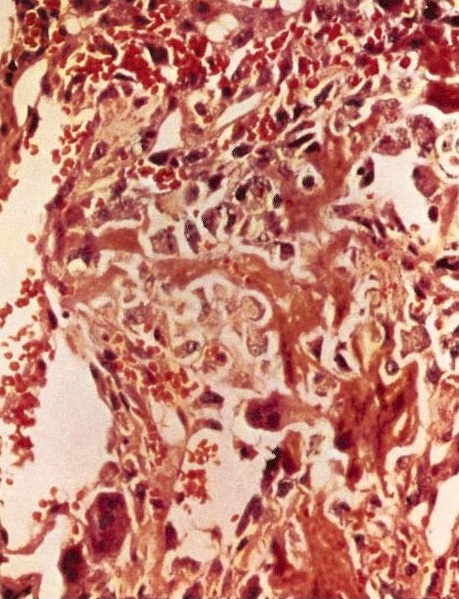

- Status postneoadjuvant chemotherapy:

- Report treatment response as a percent tumor necrosis (really an assessment of tumor drop out)

- Edematous scar: loose edematous to myxoid granulation tissue, fibrosis, mild chronic inflammation

- Bony matrix remains

- Residual tumor cells: nests of tumor cells in retraction clefts are common

- Grading response to chemotherapy (same cutoffs as Ewing sarcoma) (Cancer 1993;72:3227, J Clin Oncol 1988;6:329):

- Good response is > 90% tumor necrosis

- Report treatment response as a percent tumor necrosis (really an assessment of tumor drop out)

Microscopic (histologic) images

Contributed by Jesse Hart, D.O., Borislav A. Alexiev, M.D. and AFIP